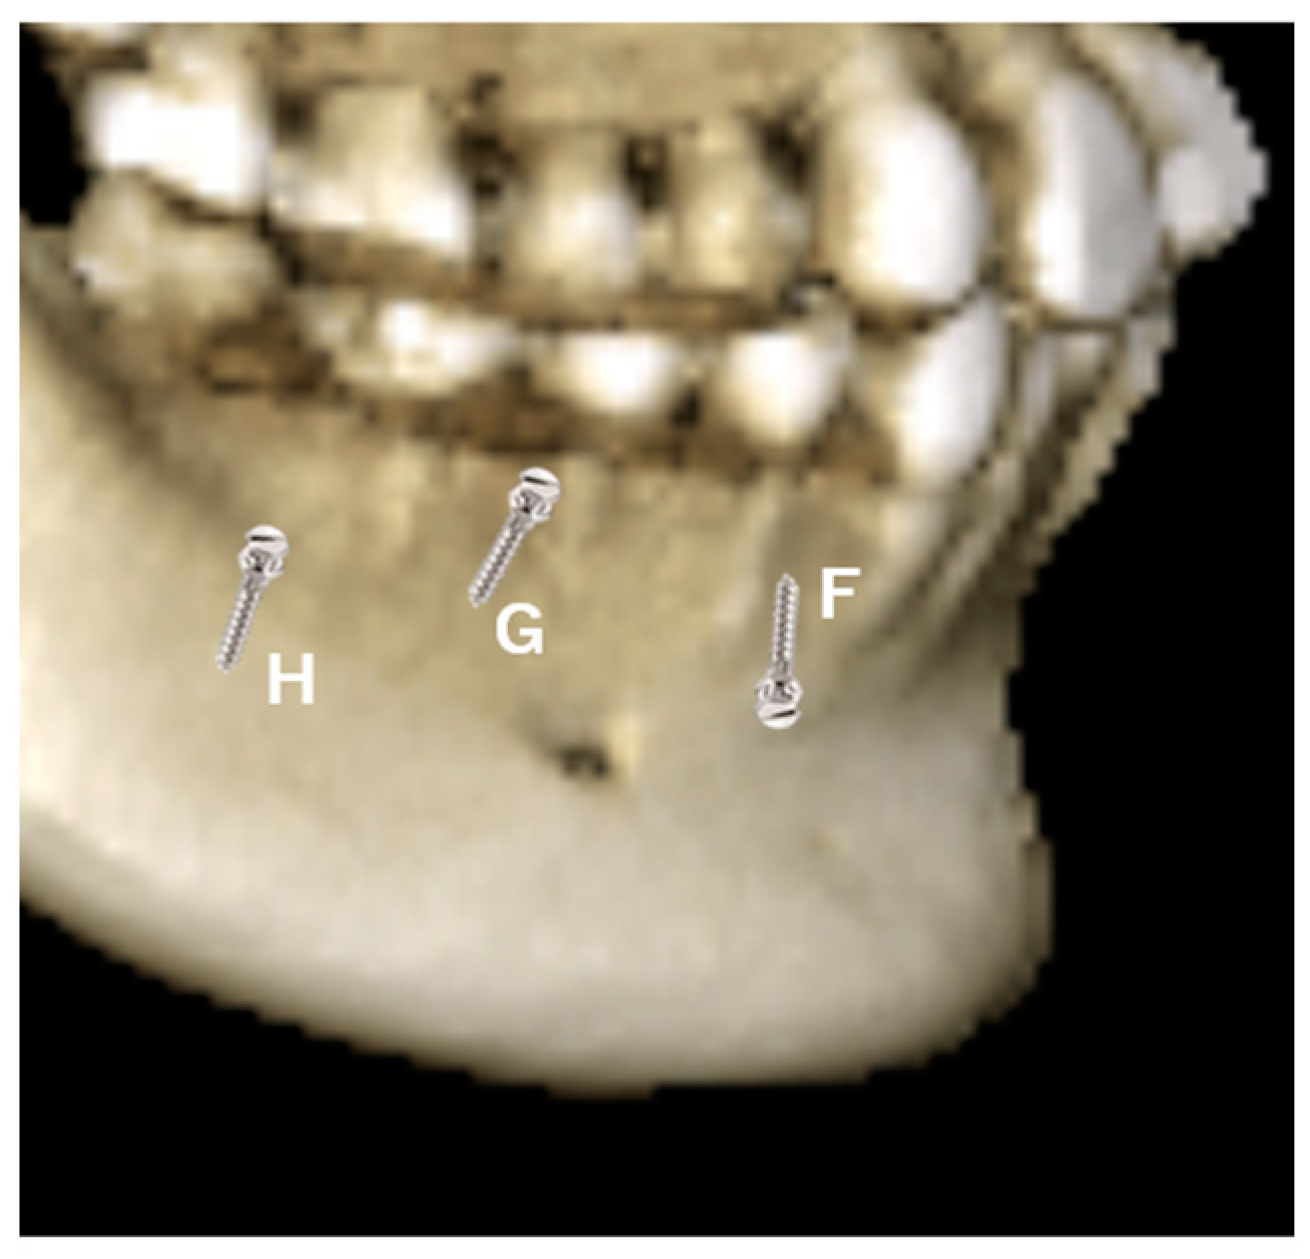

- The implantation in the interdental bone will limit the movement of the tooth, mesial and distally. Therefore, to avoid interferences with roots, the TADs are preferred on the mandible's ridge or the mandible's oblique line (Figure 3, H), especially when en-mass retraction of the arch is desirable. The ridge of the mandible between the body and the ramus of the mandible is a favorable site for TAD placement. The tricky part is that the mandible ridge may seem insignificant in women relative to men, and modification may be needed in the surgical guide’s design. Since the placement location is a steep bone wall, manual placement will be challenging, so a surgical guide is preferred. The angulated placement of the TADs in this area and the flabby mucosa also necessitates using the surgical guide. Care must be taken during the intraoral scan as the superficial mucous membrane above the ridge must be gently stretched to record this critical area. Lacking recorded data in this area will affect the visibility of the area site, and the surgical guide cannot be planned. Implantation in this area is recommended using contra-angle motorized instruments, as the buccal cheek tissue prevents using a hand screwdriver and will obstruct the surgeon's vision. The buccal musculature, maxillary teeth, and mouth opening will limit the maneuverability of the implantation procedure. These limitations should be evaluated during a clinical examination. Considering the hindrance in lower lip movements, the placement between the four incisors should be avoided as much as possible. TADS in this area can cause painful lip ulcerations with delayed healing. The location of the canine and the first bicuspid (Figure 3, F) is an area that can fit in the implantation choice. This location is between anterior and posterior dental arch segments and thus will provide an excellent place to resolve both anterior and posterior malocclusion. Depending on the extraction case or non-extraction case, considerations can be different, and placement in the extraction site of the bicuspid and adjacent area is required to avoid proximity to vital structures in the mentalis foramen. In Figure 3, G location is possible when there is a need to retract the anterior teeth after an extraction case when implantation of the ridge of the mandible is difficult or impossible due to the younger age of the patient. However, implantation at a young age, e.g., under 12, is risky as bone metabolism is still high in this area.